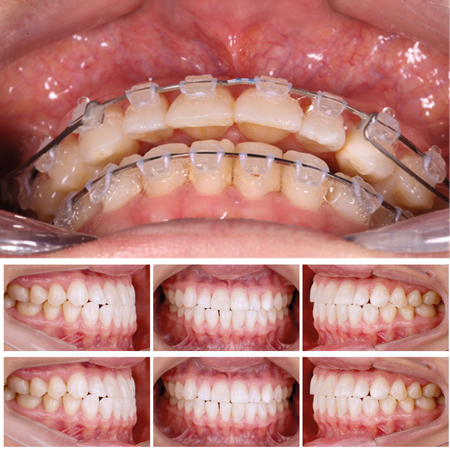

Compensación dentoesquelética extrema para mordida abierta anterior esquelética severa tratada con Invisalign

INTRODUCCIÓN: : La mordida abierta anterior es una maloclusión compleja, a menudo asociada con discrepancias esqueléticas y verticales. Con la evolución de la tecnología de alineadores transparentes, (los alineadores) Invisalign® se han convertido en una opción viable para el tratamiento de casos complejos con una planificación adecuada. CASO CLÍNICO: Este caso clínico describe el tratamiento de una paciente de 28 años con mordida abierta anterior esquelética severa y una...

Extreme dentoalveolar compensation of a severe skeletal anterior open bite with Invisalign®

INTRODUCTION: Anterior open bite is a challenging malocclusion, often associated with skeletal and vertical discrepancies. With the evolution of clear aligner technology, Invisalign® has become a viable option for treating complex cases when appropriately planned. CASE REPORT: This case report describes the treatment of a 28-year-old female patient with a severe skeletal anterior open bite and a slight Class III molar and canine relationship. The treatment involved the use of Invisalign®...